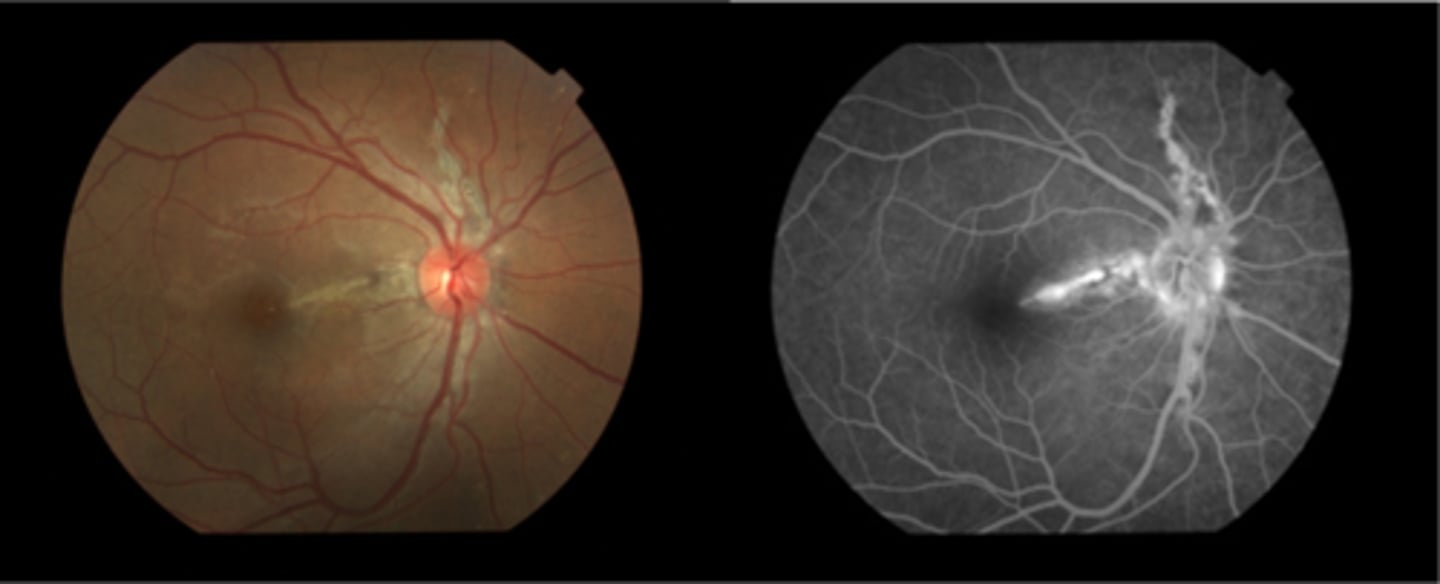

What finding of toxoplasmosis is seen in A/B?

retinitis turns into hazy scar with nerve pallor

What finding of toxoplasmosis is seen in C/D?

scarring overtime with VA loss/scotoma

What findings of toxoplasmosis are seen here?

retinal vasculitis

exudative scar

focal, hazy vitritis and retinitis

What findings of toxoplasmosis are seen here?

latent scars